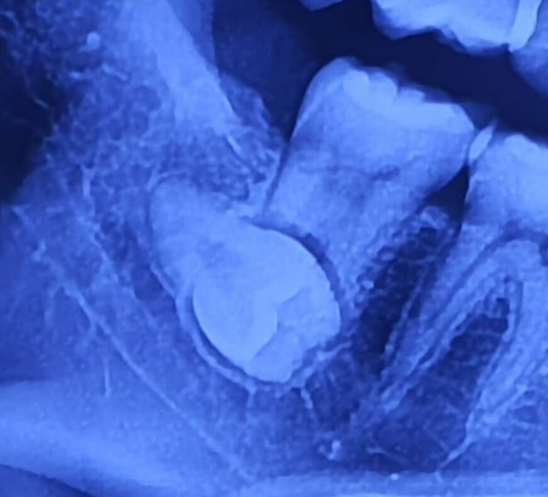

본격적인 운동을 계획 중이라면 아래의 운동 유형별 재개 시기 표를 참고해 보세요. 자신의 상태가 매복 사랑니였다면 이 기준에서 3~4일 정도 더 여유를 두는 것이 안전합니다.

| 운동 유형 | 권장 재개 시기 | 주의사항 및 이유 |

|---|---|---|

| 산책 및 스트레칭 | 발치 2~3일 후 | 저강도로 혈류를 촉진하여 붓기 완화에 도움 |

| 유산소(조깅, 사이클) | 발치 4~7일 후 | 가쁜 호흡이 혈압을 높여 재출혈 유발 가능 |

| 근력 운동(웨이트) | 발치 7~10일 후 | 힘을 줄 때 얼굴 근육 긴장 및 혈압 상승 주의 |

| 수영 및 사우나 | 발치 10일 이상 | 공용 시설의 세균 감염 및 열감으로 인한 염증 위험 |